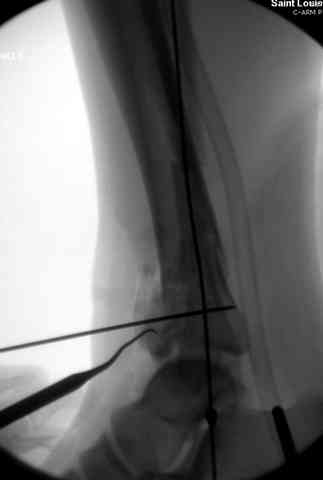

При лечении внутрисуставных переломов типа "Pilon"

или "Tibial Plateau" на голени, применение простых

наружных фиксаторов типа "Spanning ExFix" или "Travelling ExFix" стал одним из стандартом этапного лечения.

В первые часы после поступления больным экстренно накладывается простой фиксатор из двух поперечно проведенных стержней или сооружается "Delta

Frame" в зависимости от места локализации, и проводится дистракция.

Здесь выставлена пара случаев перелома пилона, оба

случая леченные этапным наружным фиксатором.